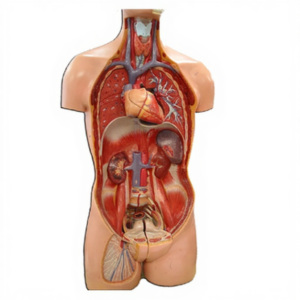

Kidney with Adrenal Gland Anatomy Model for Biology Lab

Kidney with Adrenal Gland Anatomy Model Manufacturer, Supplier and Exporter for Biology Lab – Life size model, 2 parts model of the kidney with the adrenal gland. The model is sectioned along the front plane; showing internal structures, including the

We are leading manufacturers, suppliers & exporters of Kidney with Adrenal Gland Anatomy Model for Biology Lab. to get high quality designed Kidney with Adrenal Gland Anatomy Model for Biology Lab and Lab Education & Training Products for schools, colleges, TVET, universities, training laboratory, research lab, hospital and medical lab and various Industrial Laboratory Training Program. We accept bulk orders for government tenders in all countries around the globe.